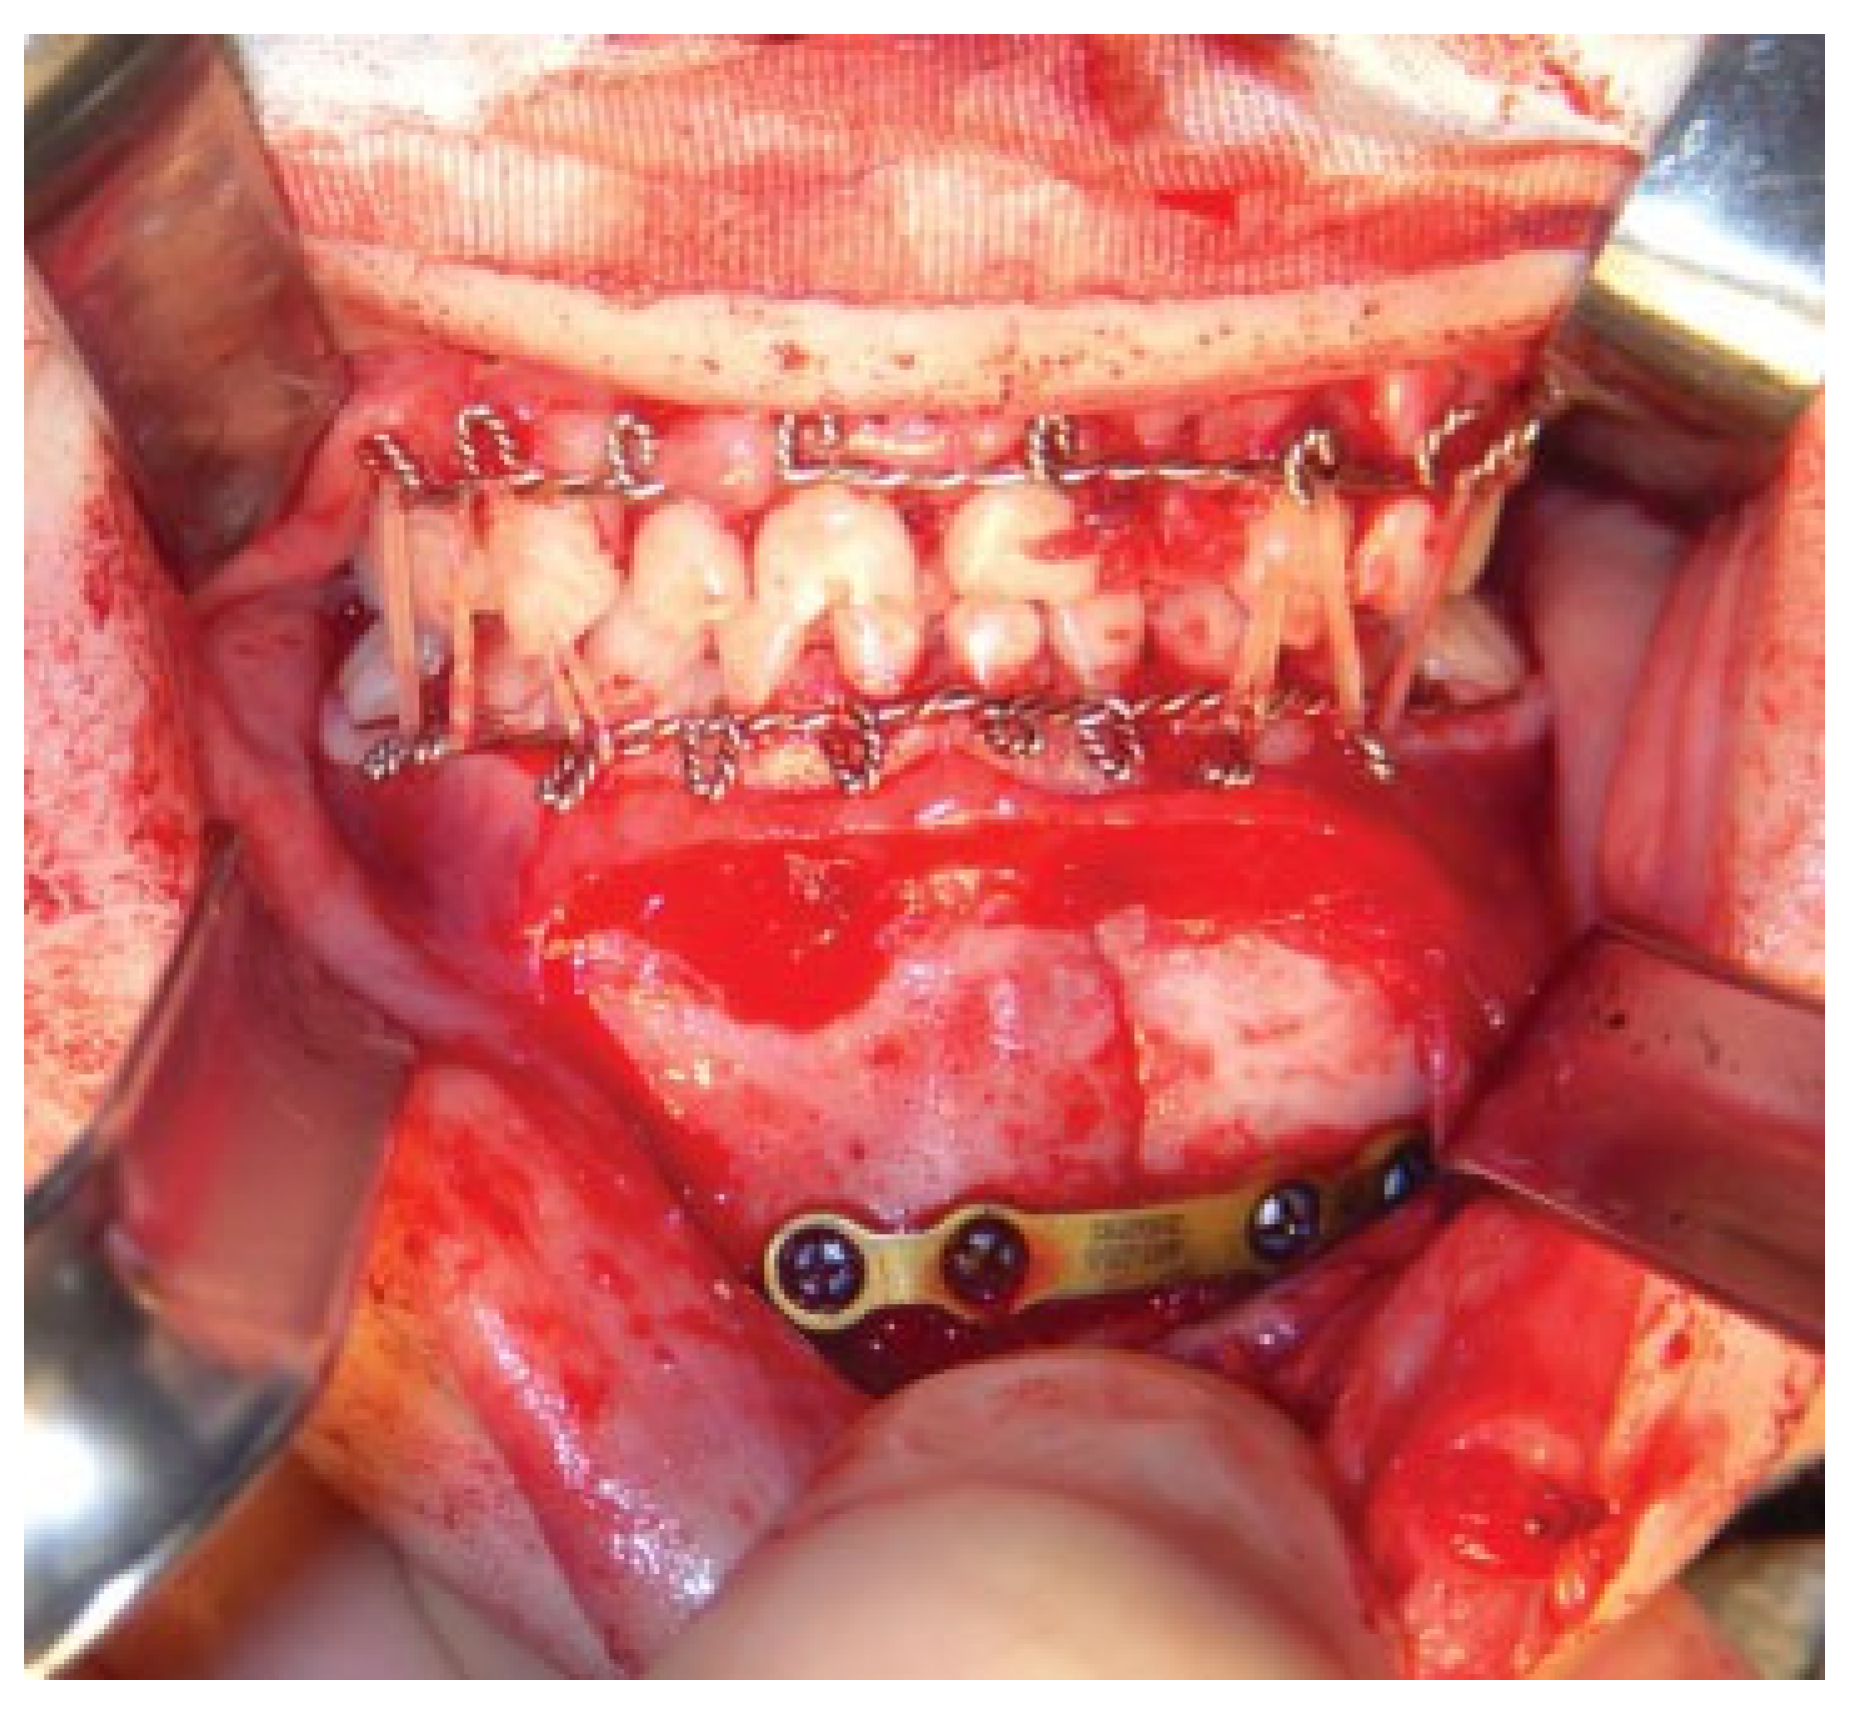

Modifications to this procedure include using 24-gauge stainless steel wire that is passed from the last molar as originally described (Figure 2). The wire is then twisted from one side of the dental arch to the other (Figure 3). Ideally, circumdental ligatures are passed to secure the individual teeth as the cable is being twisted (Figure 4). This will allow for secure fastening of the cable and ligature complex. Finally, when the wires composing the Risdon cable have reached the contralateral molar tooth, it is then secured and the final circumdental ligature is placed. The circumdental wires are cut and twisted in a traditional fashion that will allow loops for securing elastics or wiring to establish MMF or guiding functions (Figure 5). If elastics are used for MMF, it is most unusual for the Risdon wiring to pull off or otherwise fail as the elastics “give.” Aside from establishing MMF, this procedure may also be used for splinting avulsed or luxated teeth, and may be supplemented with autopolymerizing resin for stability (Figure 6). Following application of the Risdon cable, open reduction internal fixation may then be performed with the patient in MMF (Figure 7).

Figure 7. Open reduction internal fixation completed with intermaxillary fixation accomplished using rubber bands and Risdon cables.